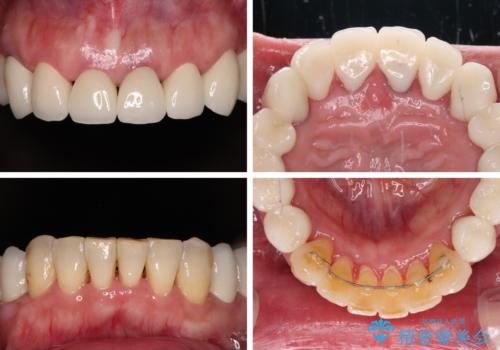

歯肉の状態が落ち着いた後に下顎の矯正治療を行い、その後補綴治療を行うこととしました。

インプラントに対する恐怖心が強く、欠損補綴は極力ブリッジを採用し、インプラントの数は必要最小限としました。

油断をするとすぐに汚れが溜まって歯肉が腫れてきてしまうため、今後も定期的なメインテナンスが重要となります。